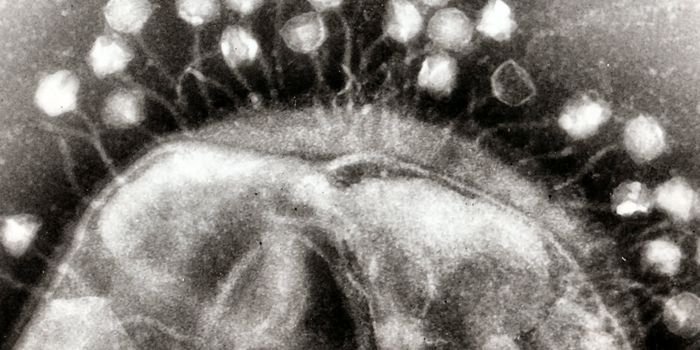

MAY 04, 2020MicrobiologyThe COVID-19 pandemic has spread around the world and there is still no available treatment or a vaccine. Prevention rem ...

MAR 17, 2020ImmunologyStructurally, SARS-CoV-2 (the virus that causes COVID-19) are spherical shells consisting of a lipid membrane, with a co ...